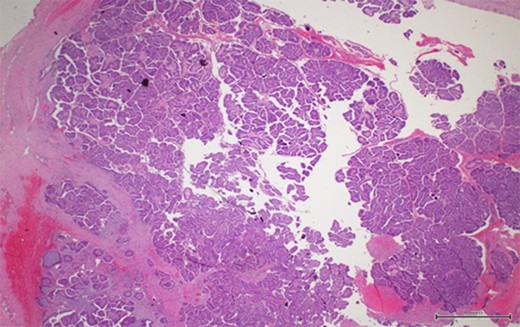

Ultrasound studies showed a well-defined solid-cystic nodule measuring approximately 2.1 cm × 2.1 cm × 1.4 cm with internal septation. There was a large, peripherally located solid component with internal vascularity seen (Fig. 2). The lesion was deemed indeterminate and an excision biopsy was performed. The histology report revealed a Grade 1 IPC with no lymphovascular invasion (Figs 3 and 4).

A thick fibrous wall surrounding a cystic space with a complex and arborizing papillary network within (magnification x2).

Scattered tubules (arrow) within the stroma with no extension beyond the fibrous wall. These scattered tubules measure 3 mm (magnification x4).